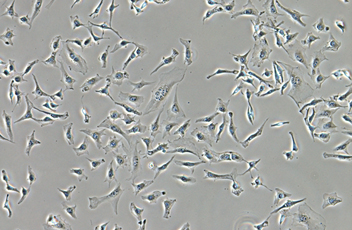

高对比度的图像与中性背景着色与放大倍数无关的范围,可以被捕获。这一观察技术适合于观察未染色结构。

相差附件和物镜